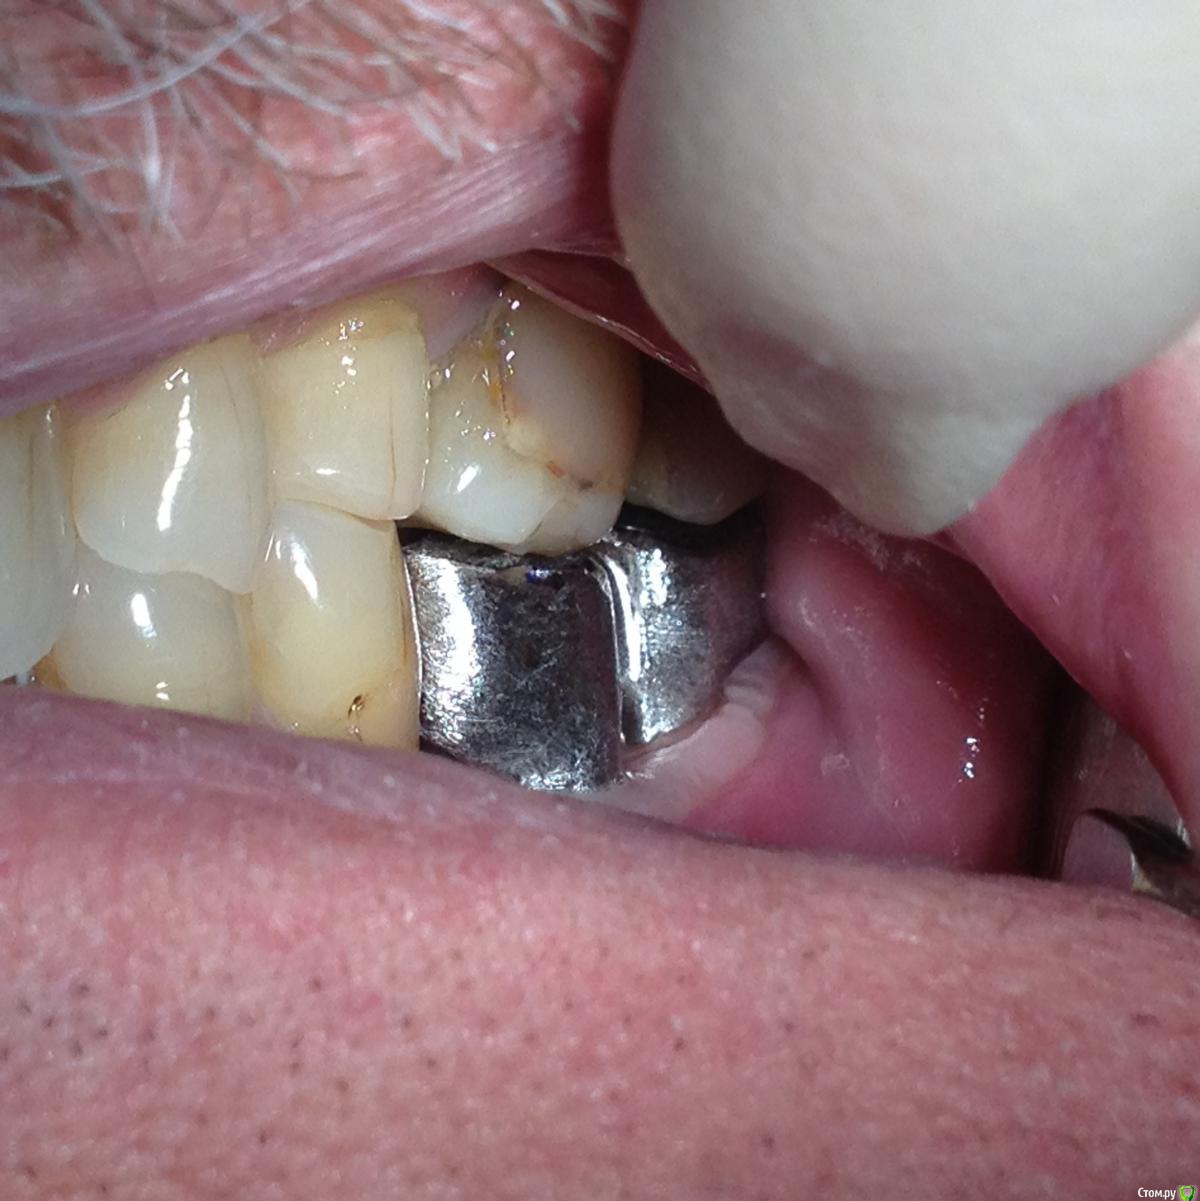

chervoncevdaniil Опубликовано 13 марта, 2016 Поделиться Опубликовано 13 марта, 2016 На фото,где вы меряете без керамики 36 и 37,почему 36 в контакте с антагонистом?Откуда место потом под облицовку взялось? Ссылка на комментарий

Shakirbura Опубликовано 13 марта, 2016 Автор Поделиться Опубликовано 13 марта, 2016 На фото,где вы меряете без керамики 36 и 37,почему 36 в контакте с антагонистом?Откуда место потом под облицовку взялось?Там контакта не было, но я техникам написал, чтоб места создали под керамику. Ну и регистрация прикуса повторная. Ссылка на комментарий

drvikont Опубликовано 14 марта, 2016 Поделиться Опубликовано 14 марта, 2016 а что с контактным пунктом?он вовсе отсутсвует Ссылка на комментарий

Shakirbura Опубликовано 14 марта, 2016 Автор Поделиться Опубликовано 14 марта, 2016 а что с контактным пунктом?он вовсе отсутсвуетКоллега, я же в посте написал, что исправлен пункт) Ссылка на комментарий

NazranDantist Опубликовано 14 марта, 2016 Поделиться Опубликовано 14 марта, 2016 (изменено) Вы показали работу техника. Ваша работа заключалась в правильном планировании, даже по этим фото виден окклюзионный замок в 4-ом сегменте, непонятно, что с зубами во втором сегменте. Да и вообще попахивает тотальной работой))) Изменено 14 марта, 2016 пользователем NazranDantist Ссылка на комментарий

diesel87 Опубликовано 14 марта, 2016 Поделиться Опубликовано 14 марта, 2016 Мне казалось винтовая предпочтительнее, я не прав?Винтовая предпочтительнее на верхней челюсти и при расположении импланта по центру окклюзионной линии. 36 и 37 наверное бы выбрал инд абатменты с цементной фиксацией. Ссылка на комментарий

Борис80 Опубликовано 14 марта, 2016 Поделиться Опубликовано 14 марта, 2016 Я бы порекомендовал обращать внимание на наклон зубов пациента , ограничивающих дефект... они очень часто наклонены в сторону имплантата и качественный контактный пункт не получается... Ссылка на комментарий

Shakirbura Опубликовано 14 марта, 2016 Автор Поделиться Опубликовано 14 марта, 2016 Вы показали работу техника. Ваша работа заключалась в правильном планировании, даже по этим фото виден окклюзионный замок в 4-ом сегменте, непонятно, что с зубами во втором сегменте. Да и вообще попахивает тотальной работой)))Небольшой замочек есть) Чем это черевато? Ссылка на комментарий

MaxDok Опубликовано 15 марта, 2016 Поделиться Опубликовано 15 марта, 2016 С гигиеной скорей всего будут проблемы . Ирригатор подарите пациенту ) Ссылка на комментарий